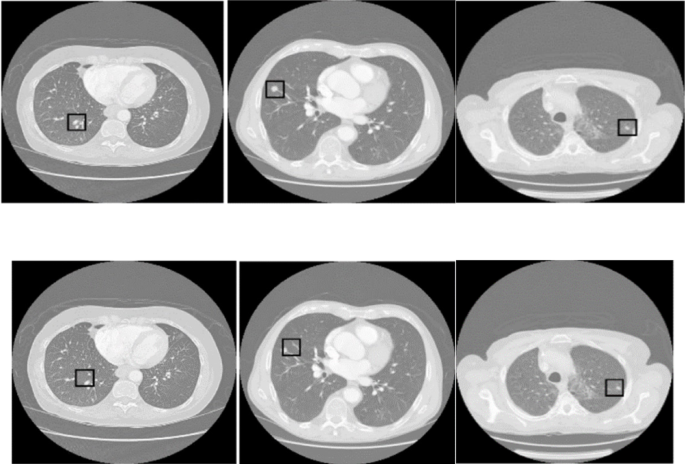

Tumor detection

Figure 6 illustrates the structure of the Mask R-CNN-based generator network for tumor detection. In this paper, our model adopts a more targeted strategy than the traditional GAN approach of generating synthetic outputs from random noise. It employs lung data from a previous step as input, sidestepping the randomness typical of conventional GANs. This deliberate input selection empowers the generator to fully exploit the comprehensive details in the lung data, producing accurate and appropriate outputs. The primary aim of the generator is to generate outputs that offer classification and precise location information. During the analysis of lung imagery, the generator categorizes various areas within the lungs, accurately labels them, and calculates their boundaries using the coordinates of the bounding box.

Figure 7 depicts the optimization flowchart for the generator used in tumor detection within the Mask R-CNN framework. The process starts by inputting segmented lung data essential for training the generator to accurately recognize and classify features in lung images. The Mask R-CNN then processed this data. In this system, the generator identifies the categories of different regions (either tumor or non-tumor) and computes bounding box coordinates that accurately pinpoint tumors in the lung scans. During training, two critical loss components are calculated: the class loss (\(\:{L}_{cls}\)) evaluates the performance of tumor classifications, and the bounding box loss (\(\:{L}_{box}\)) assesses the quality of the bounding boxes surrounding the detected tumors. These metrics provide essential feedback for refining the performance of the generator. Additionally, the discriminator calculates the adversarial loss (\(\:{L}_{adv}\)) to determine how closely the synthetic images mimic actual lung scans. This step is vital as it drives the generator to produce images that resemble real medical scans, thus enhancing the clinical applicability of the model. The optimization includes a feedback loop, continuously updating the generator based on these losses to enhance quality and realism. This prediction, loss evaluation, and updates cycle persists until the model achieves predefined termination criteria, such as reaching a maximum number of iterations. This methodical process ensures that each step boosts the efficacy of the generator, resulting in a powerful model adept at detecting tumors in lung CT images.